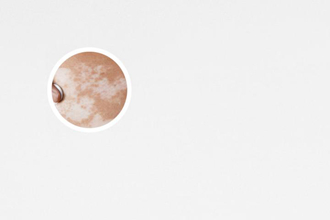

白癜風(fēng),給患者帶來(lái)了很多困擾。在治療白癜風(fēng)的過(guò)程中,311操作流程和注意事項(xiàng)是非常重要的。下面將從不同的維度來(lái)討論這些操作流程和注意事項(xiàng),幫助患者更好地應(yīng)對(duì)白癜風(fēng)。

311操作流程主要包括三個(gè)步驟:前處理、治療和后處理。前處理主要是準(zhǔn)備工作,包括清潔皮膚表面、保護(hù)周?chē)】灯つw、確定治療區(qū)域等。治療階段使用的是UVA波長(zhǎng)為311nm的燈光照射,這種波長(zhǎng)的光線能夠滲透到皮膚的深層,達(dá)到治療結(jié)果。治療時(shí)間根據(jù)病情的輕重以及病人的耐受程度而定,通常每次治療時(shí)間在幾分鐘至十幾分鐘之間。治療結(jié)束后,還需要進(jìn)行后處理工作,包括清潔皮膚、觀察治療后的反應(yīng)等。